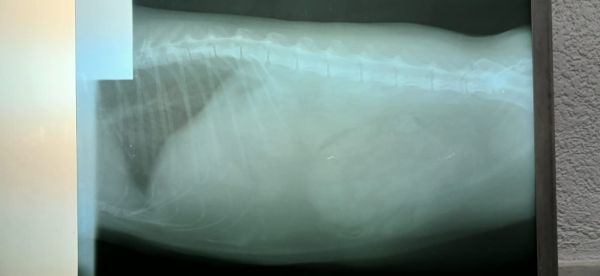

Her breathing is labored, short and shallow, even during sleep, but with a mouth closed. Her gums are pink, limbs warm, no cyanosis, no collapse. No vomiting, no diarrhea, no fever (temperature around 38°C), urinates normally. No obvious neurological deficits.

We have done an abdominal ultrasound and both abdominal and thoracic x-rays, but no abnormalities have been noticed. Her teeth are fine, but her pupils are dilated (likely because of pain or stress?)

Does this (persistent tachypnea without lung findings) sound more like:

repeat thoracic imaging?